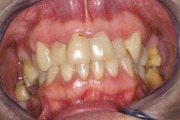

Parodontiit

Luukadu agressiivse parodontiidiga patsiendil

Agressiivse parodontiidi kahjustused rasedal naispatsiendil

GAgP 25 aastasel suitsetaval patsiendil

GAgP 25 aastasel suitsetaval puuduliku suuhügieeniga patsiendil

GAgP kahjustused 19 aastasel patsiendil